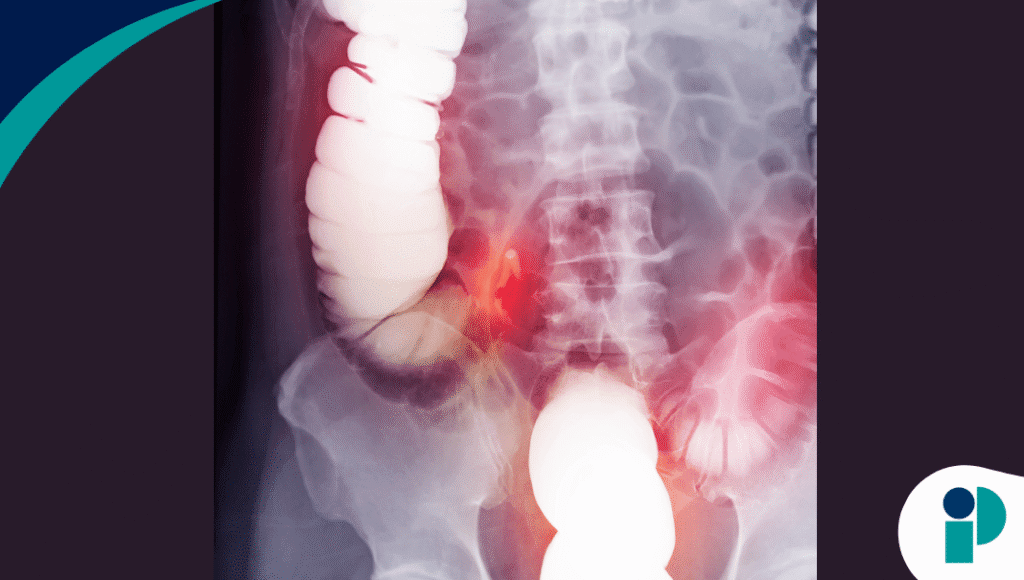

La paciente ingresó tras ingerir accidentalmente una pila de botón. Una tomografía computarizada inicial sugirió que la batería se encontraba en el bulbo duodenal, lo que motivó una endoscopia gastrointestinal superior de emergencia apenas dos horas después del ingreso. No obstante, una radiografía abdominal posterior reveló que el objeto había migrado hasta el colon derecho.

Una colonoscopia realizada ese mismo día permitió identificar que la pila se había alojado dentro de un divertículo colónico ascendente. Los especialistas lograron extraerla con éxito, evitando complicaciones graves como la perforación intestinal. Según los autores, este sería el primer caso documentado de retención de una pila de botón en un divertículo colónico.